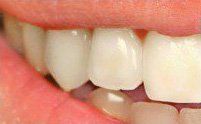

Smile Restoration Procedure

Patient needed multiple restorations, decay removed from upper teeth, crowns placed from canine to canine. Patient Missing 1st lower molar, implant and crown placed, chewing function restored. 2nd molar cracked, causing severe pain, nerve removed from tooth with root canal therapy